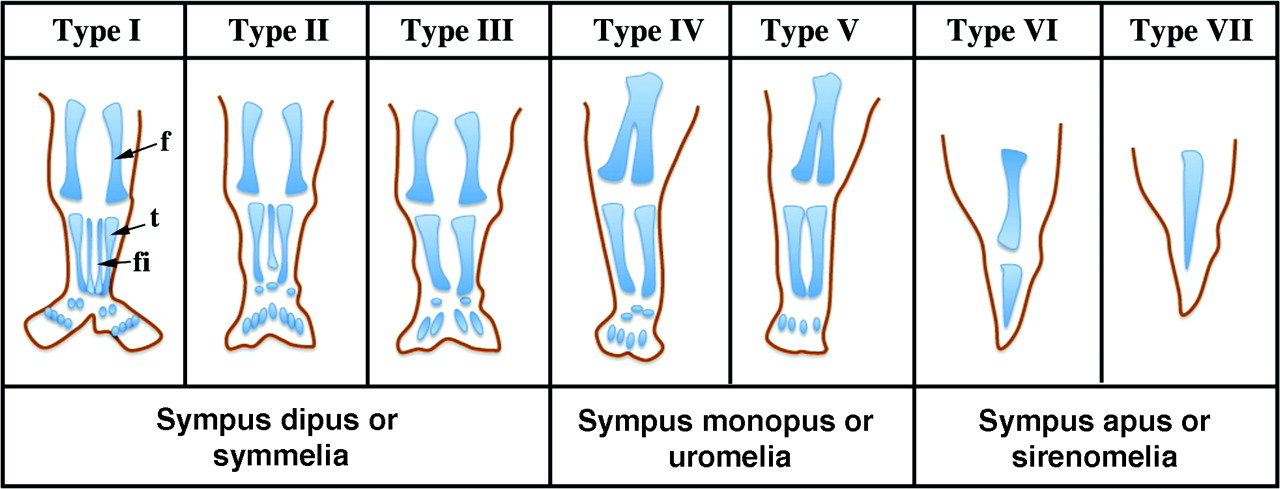

La sirenomelia se caracteriza por una fusión de miembros inferiores con alteraciones en la columna vertebral, riñones ausentes o malformados, atresia anal y sexo indeterminado en la mayoría de los casos. Frecuentemente se observa hipoplasia pulmonar y facies de Potter. La sirenomelia no debe ser confundida con ausencia de un miembro inferior. El espectro de fusión varía desde aquellos en los que se identifican todos los huesos de ambos miembros fusionados, hasta casos en los que se presenta un miembro rudimentario sin identificación de estructuras fusionadas.

Figura 2.8.4. Sirenomelia. (4 imágenes)